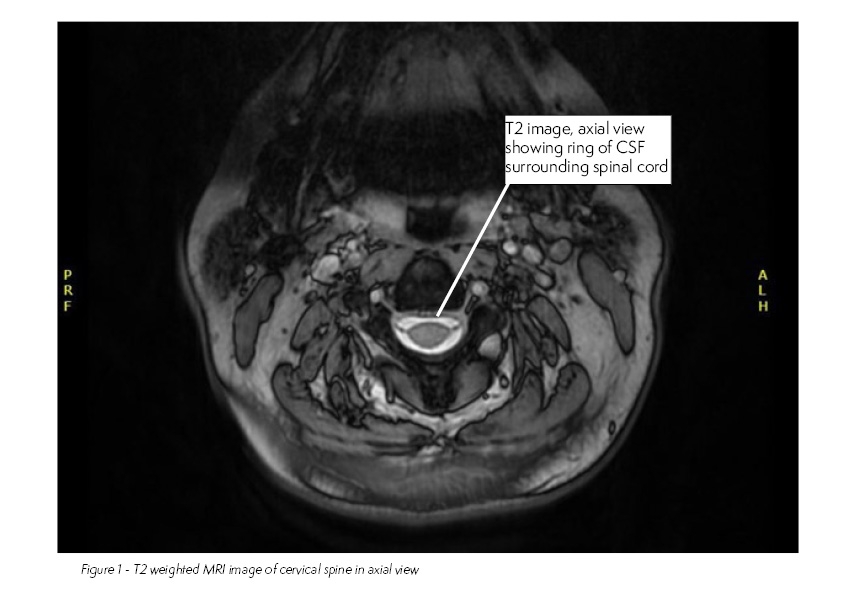

2 months later you review the MRI cervical spine that had been requested.

This patient has developed myelopathic changes of the cervical cord secondary to cervical spine stenosis.

Cervical stenosis is a relatively common condition and has been found to affect 4.9% of the adult population, with increasing incidence with age. Patients’ symptoms tend to slowly deteriorate but rapid deterioration can also occur, though many patients will be asymptomatic. Cervical stenosis can lead to radicular symptoms due to nerve root compression and myelopathy due to spinal cord compression. MRI is the gold standard investigation. Evidence of rapidly progressive neurological deficit warrants urgent neurosurgical review.